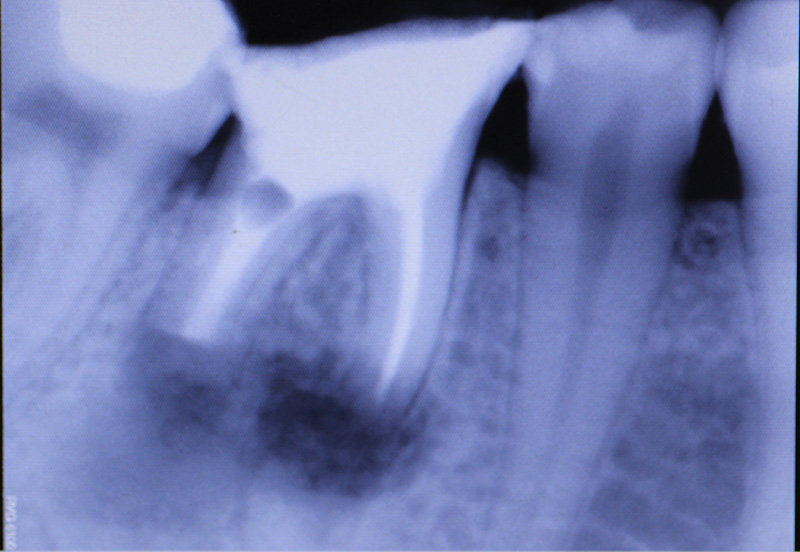

The patient underwent an operation of apicotomy (resection of the apex of the tooth root) and removed the cyst.